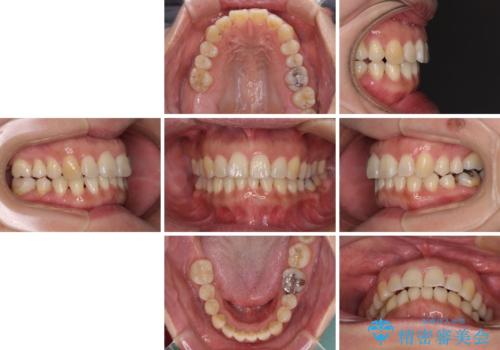

- 上下前歯の叢生を気にして来院された患者様です。

費用を抑え、期間もあまりかけずに治療をしたいとのことで、インビザライン・ライトを用いて矯正治療を行うこととしました。